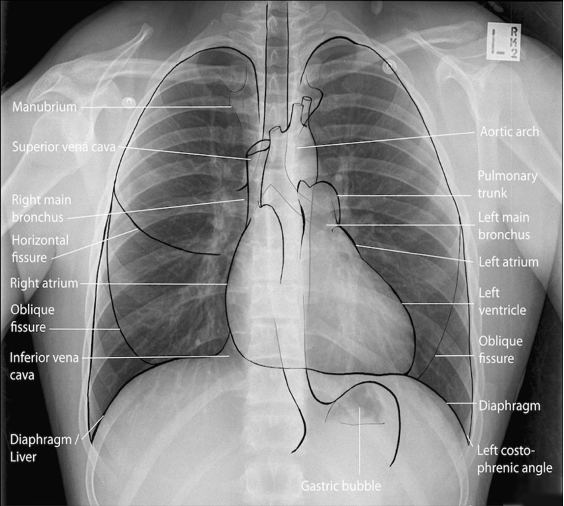

Normal rtg. af thorax:

- PA:

A

- Lateral: